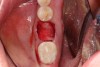

A two-wall defect is also common, usually resulting from the fracture of the buccal plate during the extraction of the tooth. As a result, a barrier membrane is necessary to contain the graft material and decrease the risk for soft-tissue invasion into the graft material (Figure 3).

Fig 3. Example of a large two-wall defect.

Figure 3